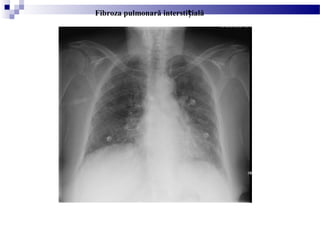

FIBROZA PULMONARĂ

INTERSTI IALĂȚ

Fibroza pulmonară intersi ială difuză are multiple cauze, cele maiț

frecvente fiind:

- idiopatice (>50%)

- boli vasculare de colagen

- agen i citotoxici i nitrofurantoinț ș

- pneumoconioze

- radia iiț

- sarcoidoza

- Din punct de vedere clinic pacien ii se prezintă cuț

dispnee progresivă de efort i tuse neproductivă;ș

- Radiologic, fibroza pulmonara intersti ială este asociatăț

cu opacită i în ”sticlă mată” în stadiile incipiente, urmândț

ca apoi să apară pierderea volumului cu opacită i liniareț

bilaterale i plămânul în ”fagure de miere”ș

- Dacă nu este efectuat un transplant de plămân,

prognosticul este nefavorabil, datorită insuficien eiț

pulmonare care apare în 3-6 ani de la diagnostic.

Fibroza pulmonară intersti ialăț

(plămâni mic ora i de volum cu opacită iș ț ț

reticulare bilaterale)

Rx torace, PA - Fibroza pulmonară idiopatică.